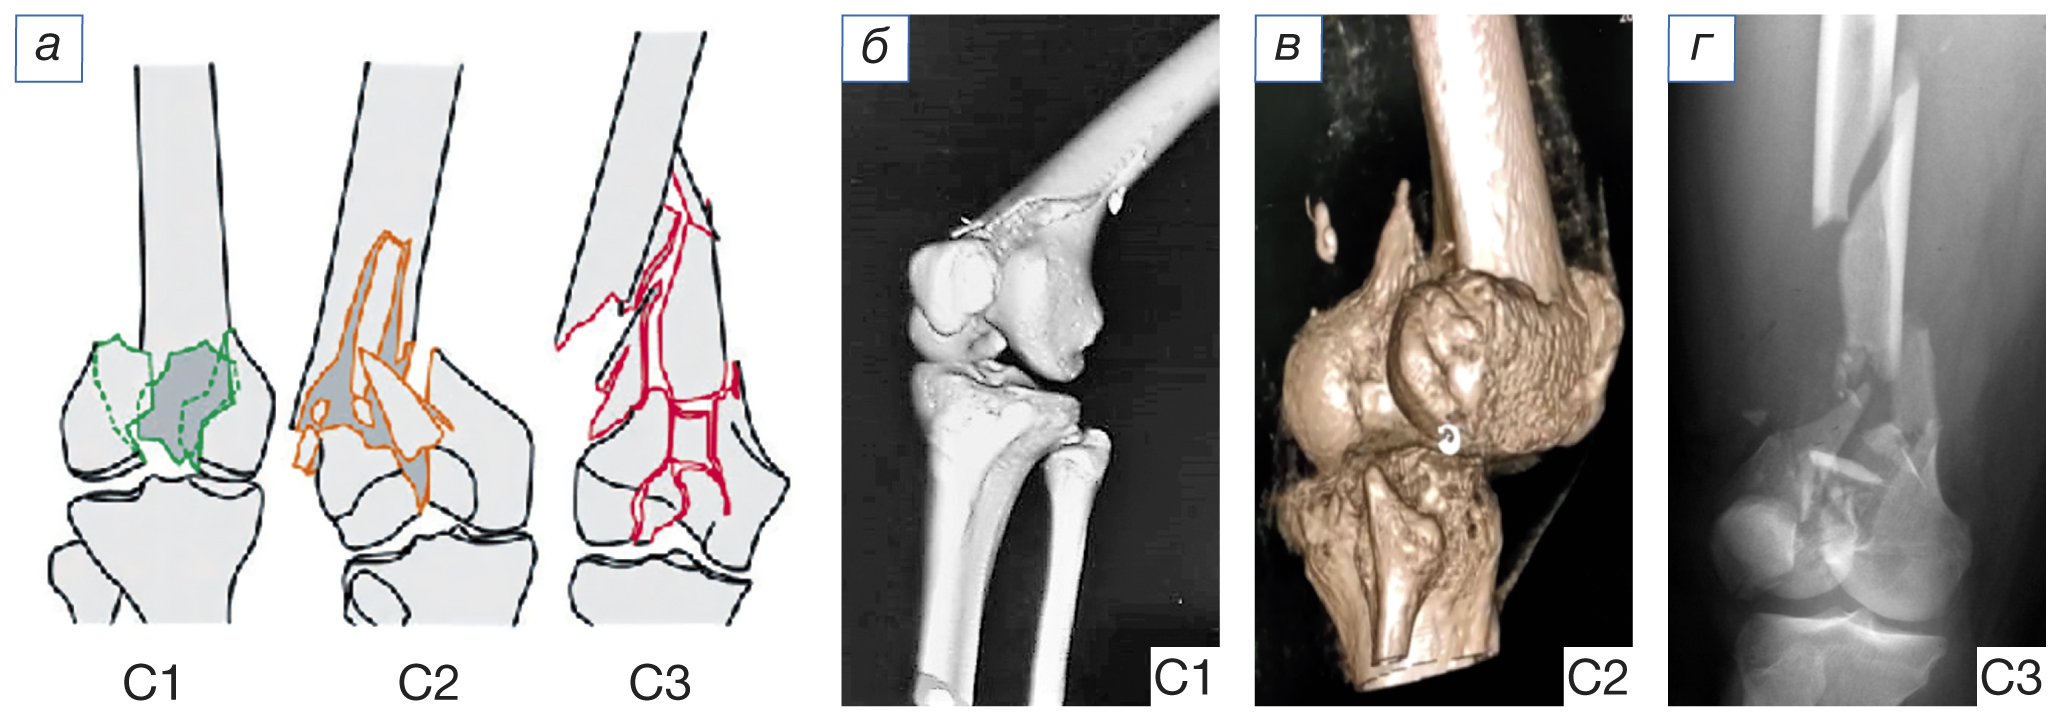

Методики остеосинтеза. Мы пользовались общепризнанной в Европе классификацией АО (Arbeitsgemeinschaft fur osteosynthesenfragen — Ассоциация по изучению остеосинтеза) для определения характера перелома дистального отдела бедренной кости (ДОБК). Выбор методики остеосинтеза перелома дистального отдела бедра зависел от характера перелома, возраста пациента, объема конечности, давности травмы, общего состояния и сопутствующих повреждений, наличия хронических заболеваний у пациента, оснащенности операционной электронно-оптическим преобразователем и имплантатами. Внутренний остеосинтез проводили лишь после противошоковой терапии, стабилизации гемодинамики и общего состояния пострадавшего. При переломах ДОБК типа С (по классификации АО; рис. 1) мы использовали интрамедуллярные штифты и ретроградную технику. Методика остеосинтеза переломов ДОБК зависела от структуры костной ткани и наличия целостного или оскольчатого характера переломов мыщелков дистального фрагмента бедра. При использовании ретроградной техники остеосинтеза штифтом переломов типа С применяли интрамедуллярный остеосинтез после предварительной репозиции и фиксации мыщелков винтами.

Рис. 1. Классификация переломов костей по АО (Arbeitsgemeinschaft fur osteosynthesenfragen): а — графическое изображение; переломы типа С по классификации АО: б — простой внутрисуставной, простой метафизарный; в — простой внутрисуставной, сложный метафизарный; г — оскольчатый внутрисуставной. / Fig. 1. C-type fractures according to the AO classification (Arbeitsgemeinschaft fur osteosynthesenfragen): а — Grafik; C-type fractures according to AO classification: б — simple intraarticular, simple metaphyseal; в — simple intraarticular, complex metaphyseal; г — comminuted intraarticular.